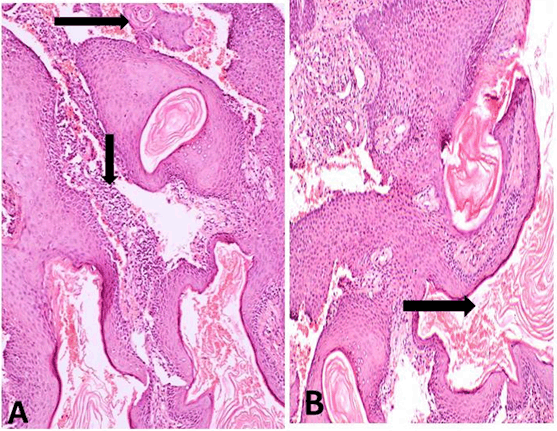

Histopathologic examination revealed a uniformly corrugated parakeratinized epithelial lining, however, some other areas showed partially uniform thickness with palisaded basal cells. A huge amount of keratin was seen filling the cystic cavity (Figure 2A-B). The epithelium exhibited basilar hyperplasia, hyperchromatism, pleomorphism, (Figure 2B), intraepithelial pearl formation (Figure 3A-B). There was discontinuity of basement membrane together with loss of polarity of basal cells in some areas (Figure 3B). The underlying stoma showed few epithelial cell nests and keratin pearls. Scattered chronic inflammatory cell infiltrate was present in the fibrous tissue capsule (Figure 4A-B) These histological findings led us to the diagnosis of odontogenic keratocyst which has undergone malignant transformation giving the diagnosis of well differentiated squamous cell carcinoma on top of keratocyst according to the presence of frank point of invasion as well as epithelial and keratin pearls in the underlying stoma.

Figure 2: (A) Odontogenic keratocysts showing a partially uniform corrugated parakeratinized epithelial lining in some parts and not uniform in other parts (H&E stain, x100). (B) The lumen of the cyst is showing a massive amount of keratin, and surrounded by epithelial lining which is parakeratinized and showing basilar hyperplasia, pleomorphism and hyperchromatism (H&E stain, x200).

Figure 3: (A) The overall presentation of the cystic space plugged with keratin and underlying connective tissue capsule showing invading epithelial element in the form of nests and pearls (H&E stain, x32). (B) High power view of the previous image showing epithelial cell nests and pearls and scattered inflammatory cell infiltrate (H&E stain, x100).

Figure 4: (A, B) The hyperplastic epithelial lining surrounding the keratin flakes filling the lumen, with keratin and epithelial pearl formation seen in the connective tissue as well as chronic inflammatory cell infiltration (H&E stain, x100).